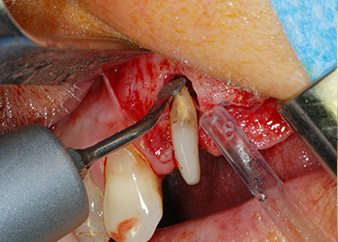

След един месец, в деня на операцията, болката и възпалението в зъб 24 е минимално, но подвижността в Miller class 2 е на лице. След отваряне на ламбата и почистването на периапикалната и перирадикуларната тъкани, обхватът на костния дефект стана очевиден (Фиг. 2 и 3).

В букалния корен, цялата вестибуларна и дистална кост липсва. Захващането е значително ограничено до палатиналния корен, подчертавайки предварително лошата прогноза. Зъб 27 също откри намалено хоризонтално захващане и минимално апикално разреждане (Фиг. 1) без клинични симптоми.

тотална загуба на кост и захват

Фиг. 2 и 3: След повдигане на ламбото, един месец след ендодонтския преглед и прилагане на цялостна периодонтална терапия в цялата уста, букалният корен на зъб 24 разкри тотална загуба на кост и захват.

Въпреки това, ние се придържахме към първоначалния си план да запазим и двата зъба като абатмънти за временен мост по време на 6-месечната остеоинтеграция на имплантите. При повторна интервенция, ситуацията трябва да се преразгледа. Първо, в опит да се овладее ендо-перио проблема, останалата повърхност на зъба е внимателно обработена с пиезохирургично оборудване (Piezomed, W&H, използван с накрайник S1 под формата на шпатула, първоначално проектиран за ерозия на латералната синусна стена) (Фиг. 4).